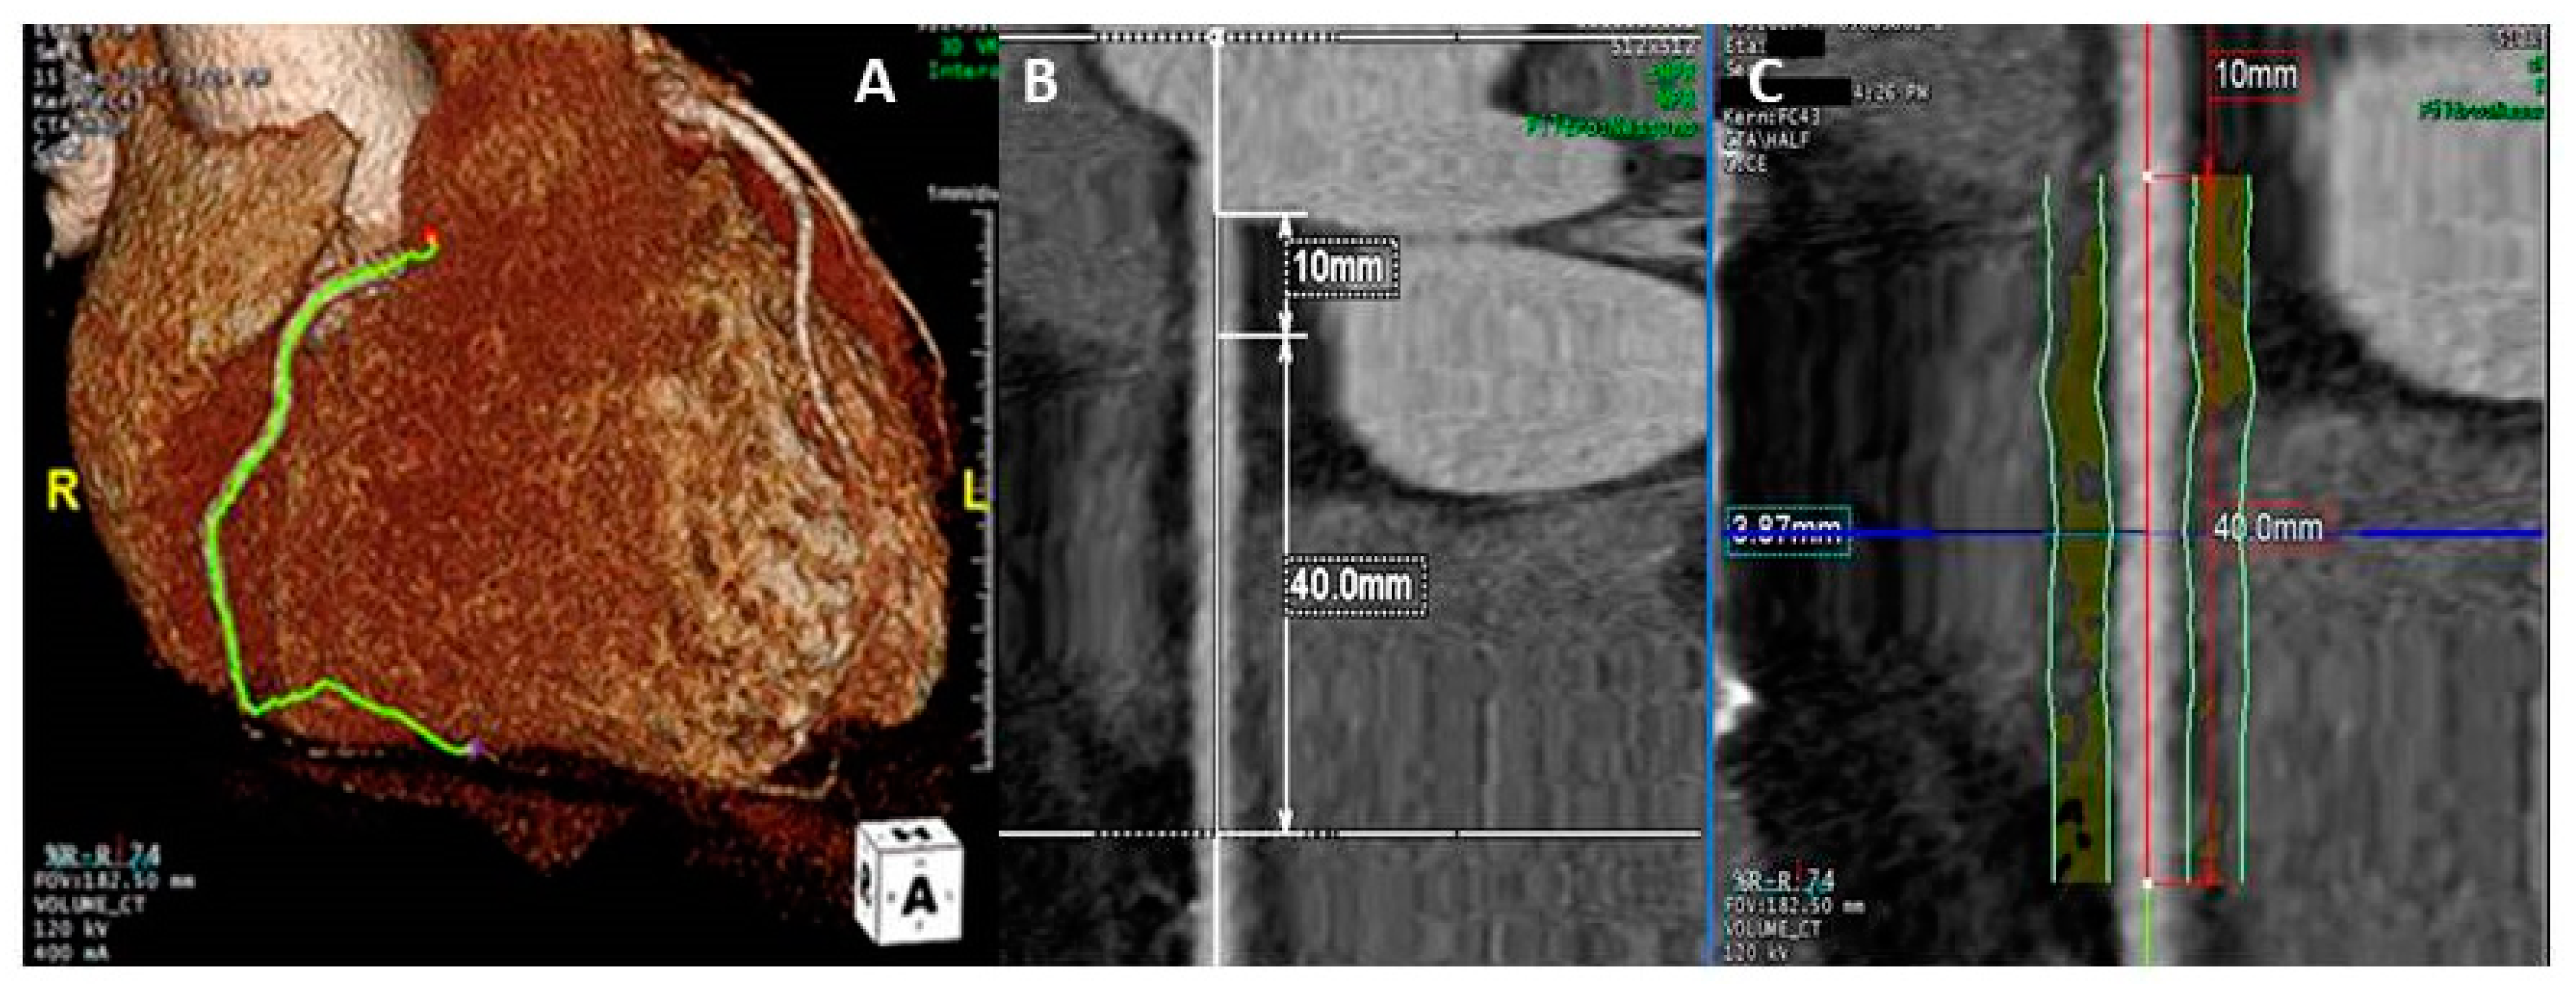

2.2. Coronary Computed Tomography Angiography